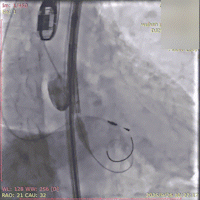

初始造影确定无冠窦

瓣膜释放过程(可见窦部扭转带来的异常轴向)

完全释放瓣膜左右重叠下评估位置

左冠切线位下立体评估左冠深浅

瓣膜脱钩

脱钩后造影

瓣膜无位移

撤出猪尾造影

无窦深约1mm

最终近左冠切线位造影,左窦深约5mm